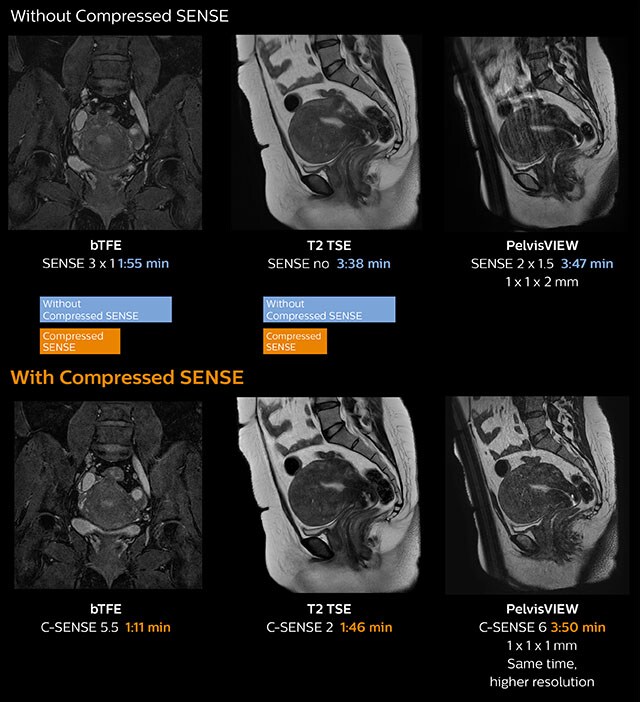

In this MRI exam of pelvis in a patient with myoma, Compressed SENSE is used to accelerate individual sequences and thus the entire examination on Ingenia 1.5T. Compressed SENSE allowed for a decrease in scan time for the T2 TSE from 3:38 to 1:46 minutes. The Compressed SENSE images in this case show fewer motion artifacts than the images from the previous protocol with SENSE. In 3D PelvisVIEW, the Compressed SENSE images have a higher and isotropic spatial resolution with a scan time similar to the SENSE sequence. The improved spatial resolution and better contrast in the myometrium of the uterus allowed radiologist Dr. Koyama to confidently diagnose the cancerous lesion in the uterus. The use of Compressed SENSE accelerates scanning times and increases spatial resolution in 3D PelvisVIEW.